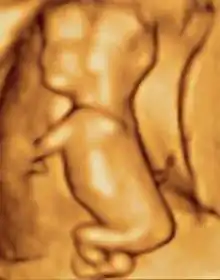

صور تخطيط الصدى ثلاثية الأبعاد المتقدمة توفر تفاصيل أكبر لتشخيص ما قبل الولادة، أكثر من تقنيات تخطيط الصدى ثنائية الأبعاد القديمة.[6] على الرغم من أن ثلاثي الأبعاد له شعبية كبيرة لدى الآباء الذين يرغبون بالحصول على صورة كتذكار[7] إلا أن إدارة الغذاء والدواء لا توصي باستخدام أي من ثنائي الأبعاد أو ثلاثي الأبعاد في غير الاستخدامات الطبية،[8] ولكن لا توجد دراسات حاسمة تربط تخطيط الصدى بأية أعراض جانبية طبية.[9] صور تخطيط الصدى ثلاثية الأبعاد التالية التقطت في مراحل مختلفة من الحمل:

جنين عند 17 أسبوعا.